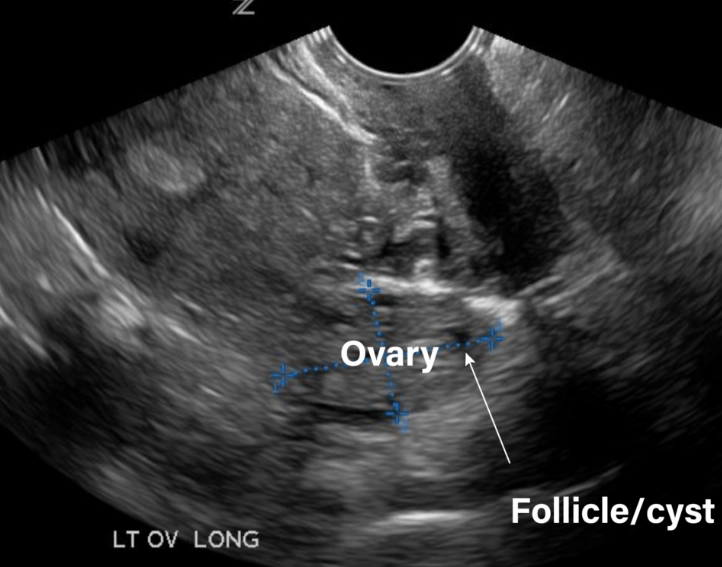

3. Structural and Anatomical Integrity

Healthy ovaries are free of large cysts that disrupt function, endometriosis implants, or scar tissue (adhesions) that can strangle blood supply or distort anatomy. Recurrent ovarian cysts aren't always "bad luck"; they can signal an underlying hormonal imbalance that needs addressing.

Transvaginal Ultrasound: Looks at ovarian volume, antral follicle count (AFC), and checks for cysts or abnormalities.